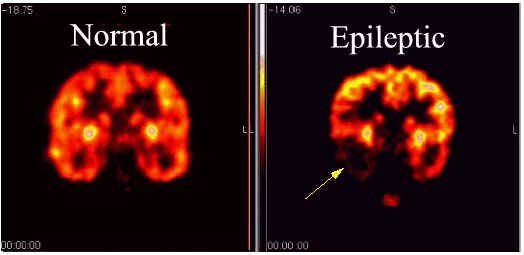

Epilepsia - El flujo sanguíneo y la captación de glucosa se miden por la PET con el fin de identificar los sitios ataques en el cerebro.En el 80% de los pacientes hay un aumento en el flujo sanguíneo y el metabolismo de la glucosa durante un ataque en la corteza cerebral. Sin embargo, entre crisis tiende a haber una menor captación de glucosa normal y el flujo sanguíneo.